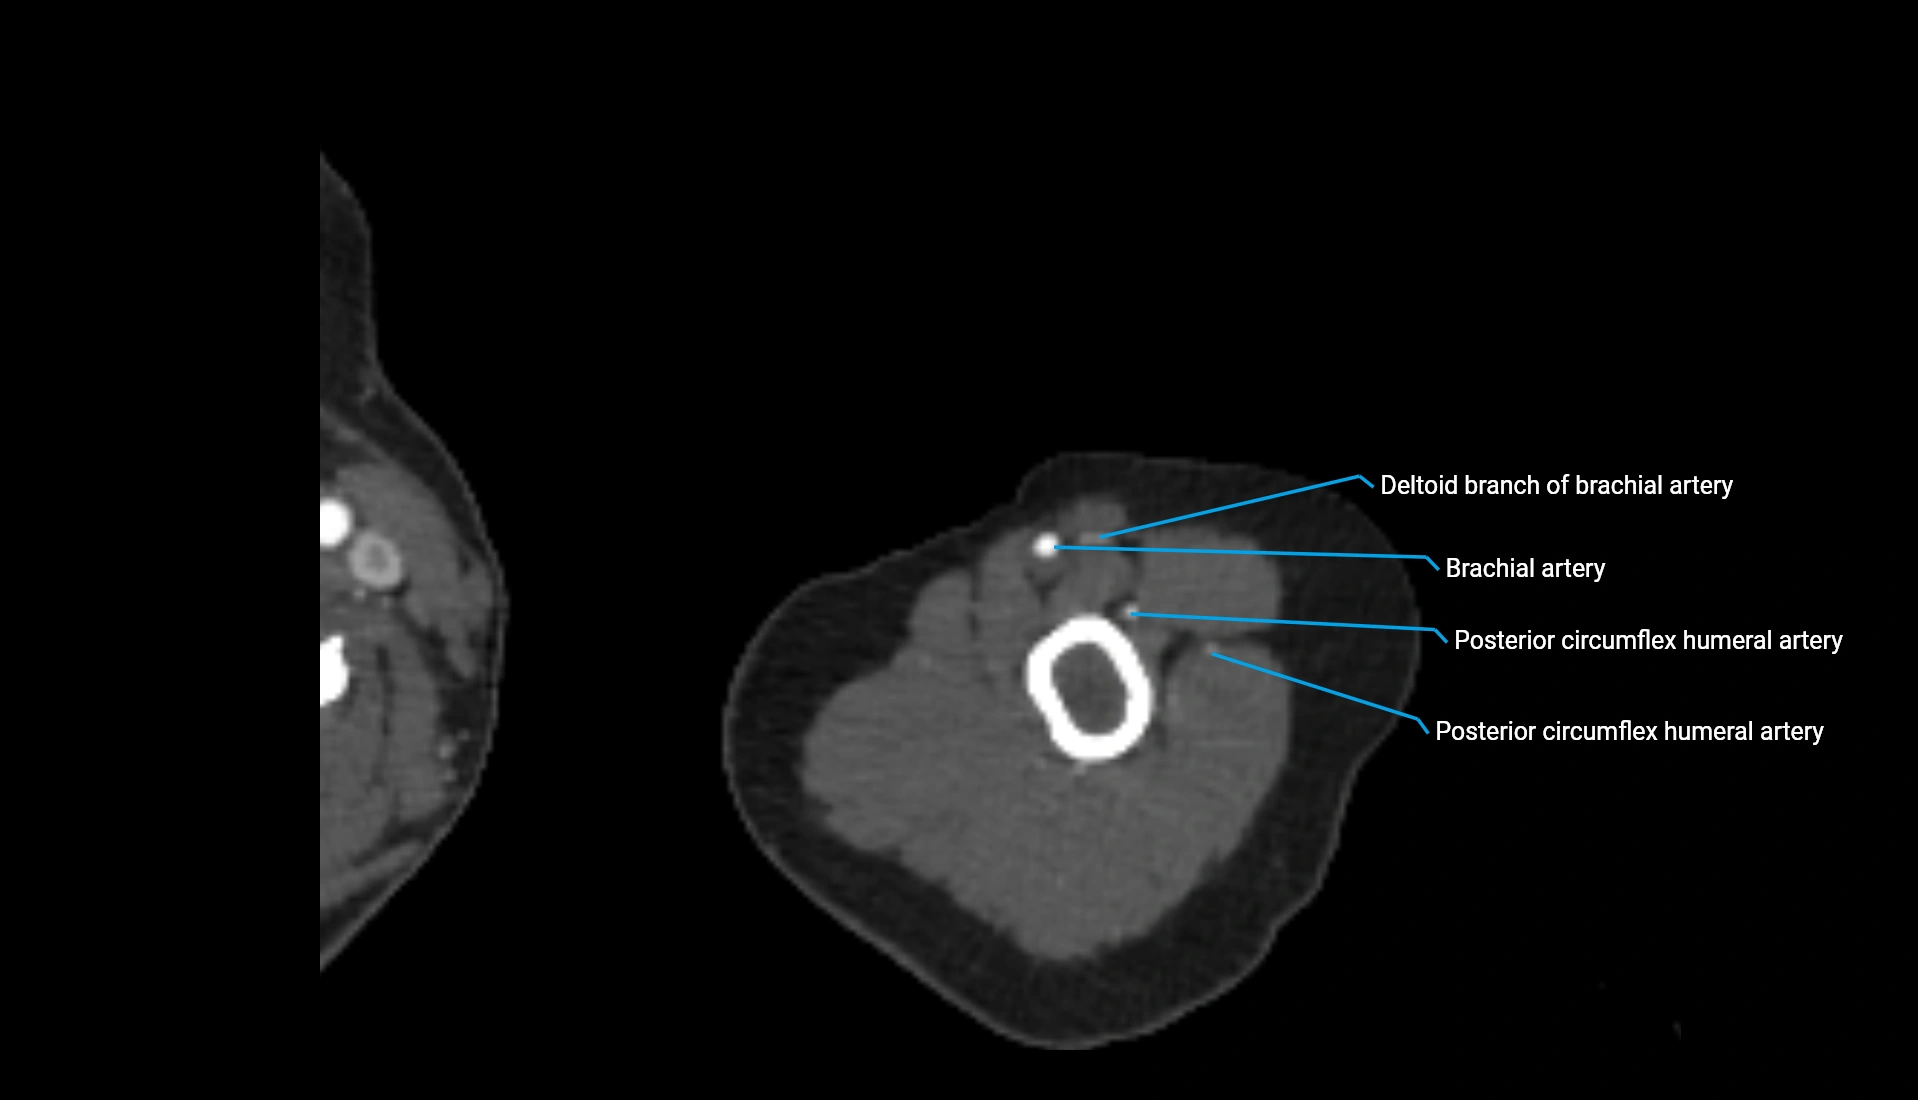

CT Appearance

Non-Contrast CT:

• Cortex: High-density, sharply defined

• Subchondral bone: Dense cancellous matrix

• Articular surface: Smooth concave contour articulating with the capitellum

• Excellent for evaluating bone integrity, alignment, and subtle fractures